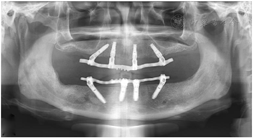

(5)术后复查:术后1个月、5个月复诊,上下颌过渡义齿咀嚼功能较戴用可摘义齿明显改善,面型及发音正常。X线全颌曲面体层片显示种植体骨结合良好(图10)。

种植修复后1、2、4年随访X线全颌曲面体层片显示种植体周围骨结合良好(图13A~C),患者对修复体美观及咀嚼功能效果满意。修复后6年(2022年8月)随访X线全颌曲面体层片及根尖片显示种植体周骨结合良好,上前牙区种植体颈部骨吸收约1 mm(图13D、图14)。取下上下颌义齿,清理义齿组织面滞留菌斑,清洁复合基台并检查基台中央螺丝稳定,清洁义齿组织面,戴回上下颌义齿(图15)。患者口腔卫生宣教,指导正确刷牙,使用冲牙器冲洗义齿与牙龈间缝隙,嘱6个月复查、维护。